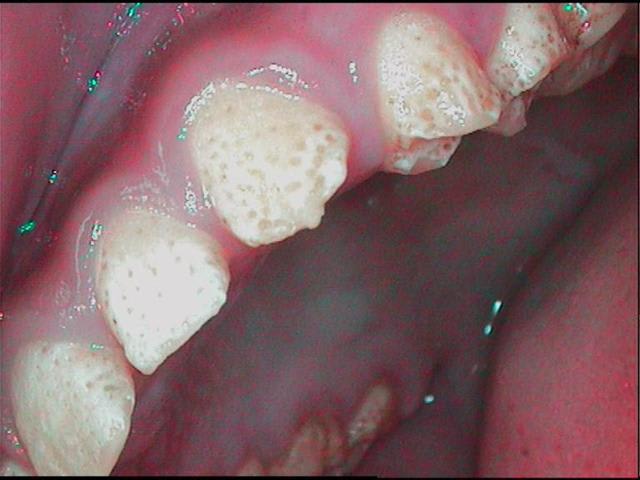

jeune patiente 11ans, je l'ai suivie il y a quelques années, pour les lacteales et sans probleme.

je la revois aujourd'hui, 11ans, et la denture definitive ne dit rien de bon pour son avenir....

je connais la famille, il n'y a aucun antécédent (connu), le controle de plaque est tres bon (elle a gardé en memoire les conseil d'hygiène, tant mieux et heureusement!!!), sa santé generale est tres bonne, ses habitudes alimentaires ne me laisse rien craindre...

pour les anterieures j'aimerais eviter les facettes, et m'orienter vers des prepa pelliculaires, pour les post je peux sceller les puits et fissures aux verres ionomeres, mais pour le "piqueté" général d'email, en buccal interprox, etc...

alors, je l'ai suivie petite, enseigné le brossage et elle a visiblement bien reçu!!!heureusement car je n'ai pas (encore?)vu en bouche la moindre amorce de carie...

pour le fluot, oui, c'était à l'époque ou je donnais du zymafluor...